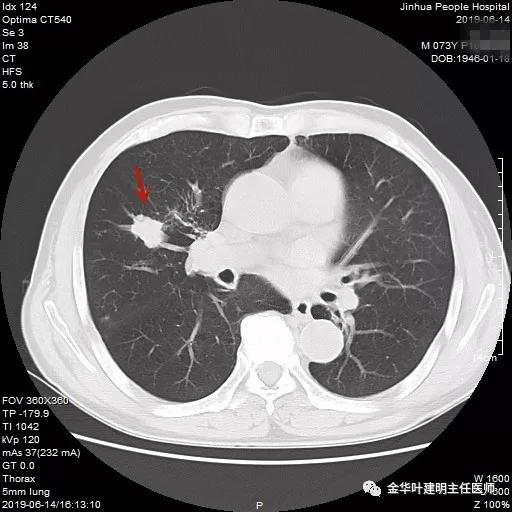

武义的吴某,今年已经73岁了,患有慢性支气管炎与肺气肿多年,每到天气转凉就要胸闷、气急及咳嗽、咳痰发作,严重时还有喘憋症状,每年都要住院1-2次。今年4月份的时候吴某又因慢支急性发作来我院呼吸内科住院。常规检查时发现右肺上叶有一实性结节,约1.5厘米大小,有毛刺及浅分叶,考虑肺癌可能性大,医生建议其行肺穿刺活检。当时图片如下: